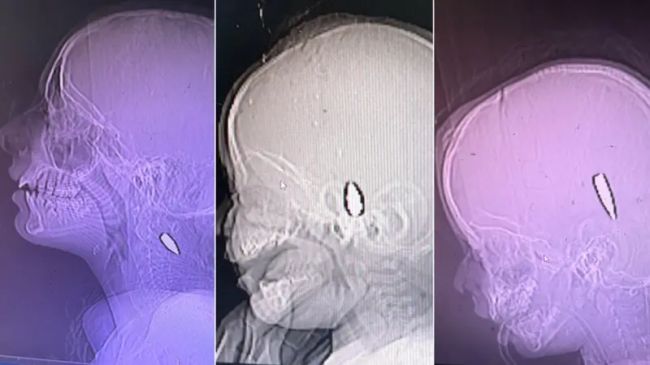

او گفت بیشتر جراحتهای ناحیه سر را جراحان مغز و اعصاب درمان میکردند، اما عکسهای رادیولوژی نشان میداد که «گلولهای درون مغز یک کودک سهساله فرو رفته بود».

تصاویر پزشکی نشان میدهد که گلولهها در بدن کودکانی با سنین ۱۲ سال، ۸ ماه و ۴ سال (از چپ به راست) باقی ماندهاند. بیبیسی نتوانسته سرنوشت همه موارد را تایید کند، اما کودک وسط جان باخته و کودک سمت راست زنده مانده استما همچنین شهادتهایی از شاهدان عینی و اعضای بازمانده خانوادهها - برخی از طریق سازمانهای حقوق بشری - گردآوری کردیم و گزارشهای رسانهای را جمعآوری و راستیآزمایی کردیم.بر پایه این اطلاعات، جزئیات مربوط به ۱۶۸ کودک را که هدف گلوله قرار گرفته بودند گردآوری کردیم؛ تنها در مواردی که توانستیم مستنداتی از جراحتها مشاهده کنیم.